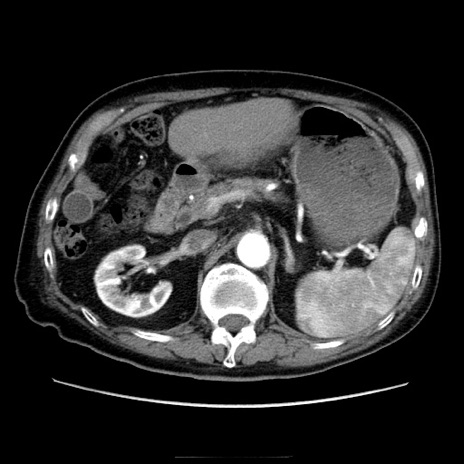

症例21(横断像)

【症例】70歳代男性

【主訴】腹痛

【現病歴】肝硬変・肝細胞癌にてかかりつけの方。約9時間前に食後より腹痛出現。症状が徐々に増悪し、嘔吐出現したため来院。

【既往歴】肝硬変、肝細胞癌(RFA、TACE後)

【身体所見】意識清明、表情苦悶様、BT 36℃、BP 129/78mmHg、P 88bpm、SpO2 97%(RA)、右上腹部から心窩部にかけて圧痛あり、反跳痛なし、筋性防御あり。

【データ】WBC 5800、CRP 0.16